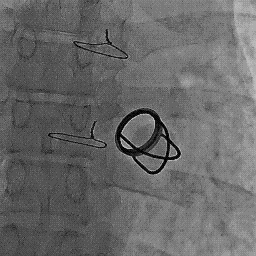

Who killed Starr -Edwards valve ? » STARR EDWARDS VALVE